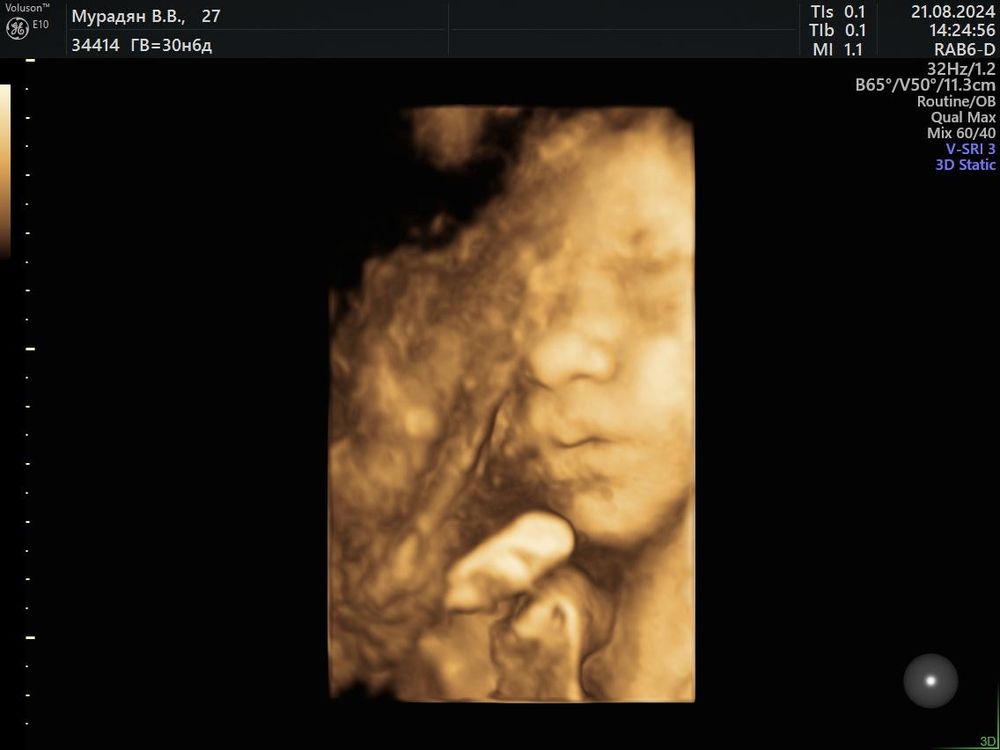

31 неделька , 3 ий скрининг 💖

Вес сыночка 1 кг 720 грамм, по скринингу все хорошо) не хотел лицо полностью показывать, лежит малыш в головном уже, до встречи осталось совсем немножко ❤️